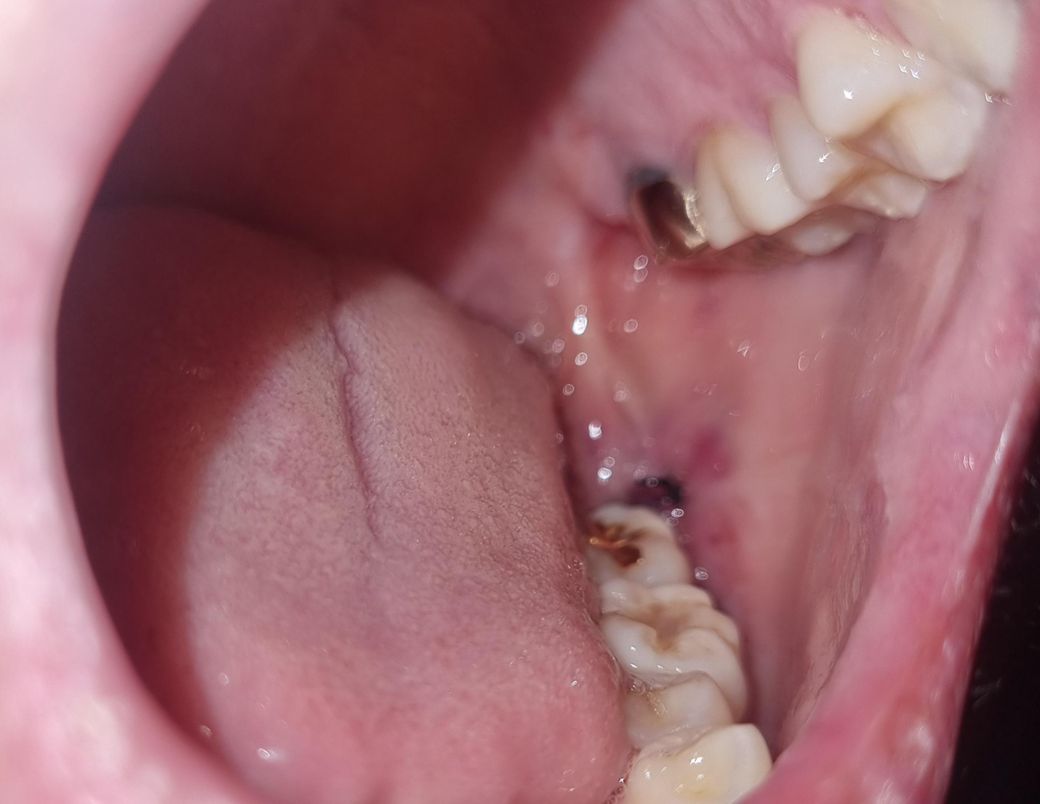

어제 오후에 왼쪽 윗,아래사랑니뽑고 그앞에있는 왼쪽 윗어금니(크라운) 윗부분이 약간회색? 이되었습니다. 저회색부위를 만졌다가 뭐잘못될까봐 일단 만지지는않았고 혀로 만졌을때 크라운이 흔들리지는않습니다. 통증x

• 1번 째 사진

1,2. 발치하면서 옆 치아를 건드려 크라운이 약간 벗겨진 것일 수도 있는데 만약 그랬다면 교합 안맞고 바로 알아차립니다

그보다는 애초에 크라운 변연이 짧아서 치아가 노출되어 있는 상태거나 아니면 잇몸퇴축으로 점차 드러난 것 같습니다

사진에 보이는건 치아 색이 변한게 아니라 나이가 들면서 잇몸이 내려가면서 치아가 노출되서 치아가 보이는겁니다. 단순 발치엿다면 3일정도 지나셧고 지혈도 됫고 통증도 없다면 운동을 하셔도 됩니다.

금리로 씌운 부위의 경계 부위는 착색 등으로 인해서 색이 어두워 보일 수 있습니다.